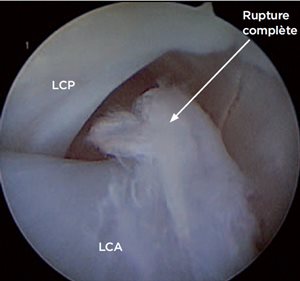

Photo 4 : Rupture partielle du ligament croisé postérieur.

LCP : ligament croisé postérieur.

En revenant médialement, ils sont inspectés (Photo 3). Le grossissement et l’apport de lumière de l’arthroscope permettent de voir des lésions qui n’auraient pas été identifiées à l’œil nu, de rechercher des ruptures partielles ligamentaires (Photo 4).

Ces dernières sont une difficulté diagnostique puisqu’elles ne sont pas toujours associées à un signe du tiroir.